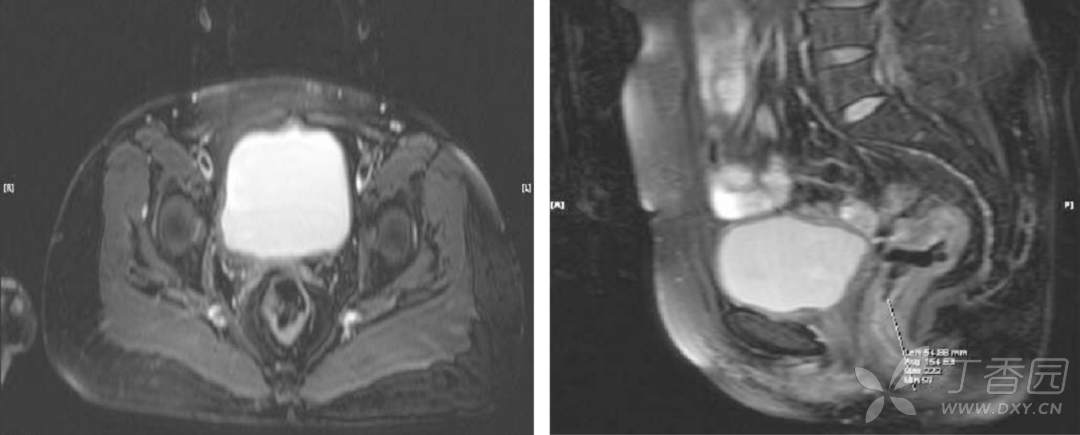

盆腔 MRI:

术前分期:直肠癌 cT2~3NXM0